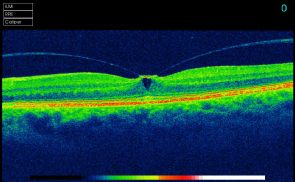

Optical Coherence Tomography uses low intensity infra-red light to give a 3D image of the back of the eye. It shows not only the surface but also the depth of the structures. It is similar to using ultrasound and creates an image not unlike an MRI or CT scan.

The instrument is incredibly good at measuring and monitoring Macular Degeneration. It can measure the thickness of the optic nerves which are affected by Glaucoma (and compare to an age, gender and ethnically matched normal).

In both circumstances it can mathematically show any changes from one visit to the next, working at a level way beyond the ability of even the most experienced observer with normal viewing methods.

Everyone can have greater reassurance from a more in-depth examination. The two main areas where we see benefits are to people with, or likely to develop, Macular Degeneration (mainly people aged 60 or over) and those with a family history of Glaucoma or high pressures in their eyes. Diabetics can be monitored and compared more accurately, which is very beneficial in the long term.